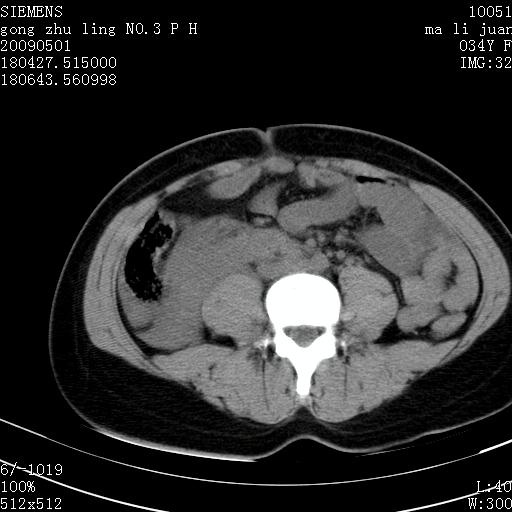

标题: CT19733:右肾碎裂

青年女性,骑摩托车摔伤。

右肾碎裂伤,包膜下血肿。

术中仅见右肾碎裂,肾蒂血管未见断裂。

支持 右肾破裂伴肾包膜下及肾周血肿。

右肾破裂并右侧腹膜后间隙出血。